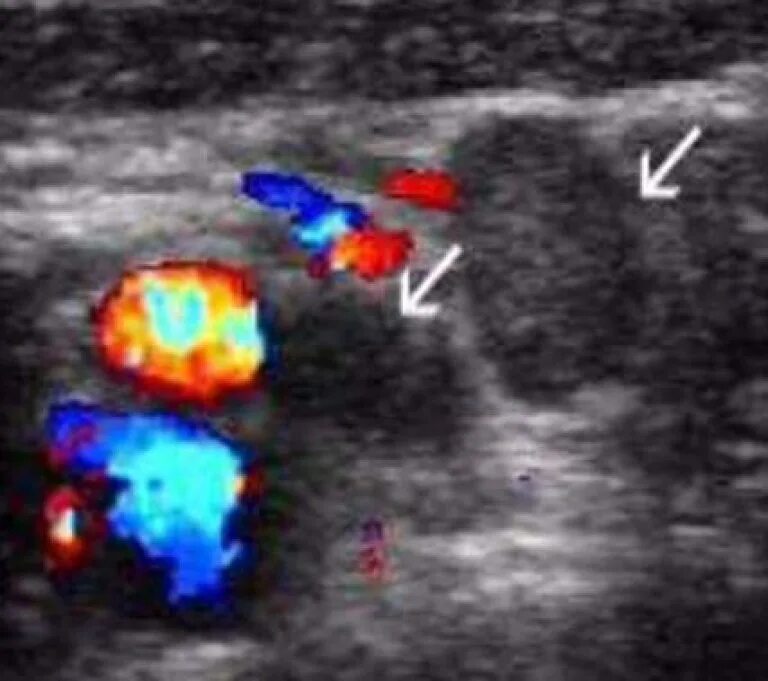

Лимфоузлы гиперплазированы